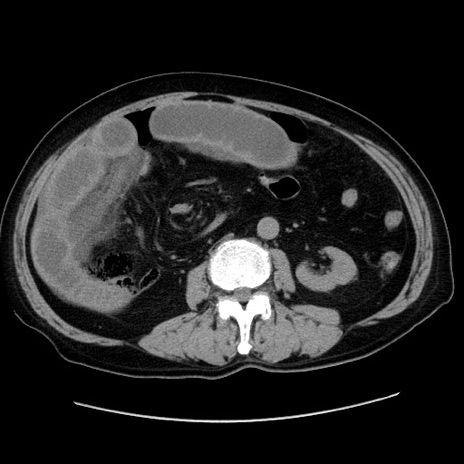

症例30(横断像)

【症例】80歳代男性

【主訴】臍周囲痛

【現病歴】約6時間前から臍下部痛が出現。次第に腹部膨隆・背部痛も生じてきたため来院。背部痛の場所は変化しない。

【身体所見】意識清明、BT 36.3℃、BP  131/87mmHg、P 87bpm、SpO2 100%(RA)、臍周囲自発痛・圧痛あり、反跳痛なし、自発痛部位に一致して板状硬あり、腹部膨隆、腸雑音減弱、CVA tenderness両側陰性。